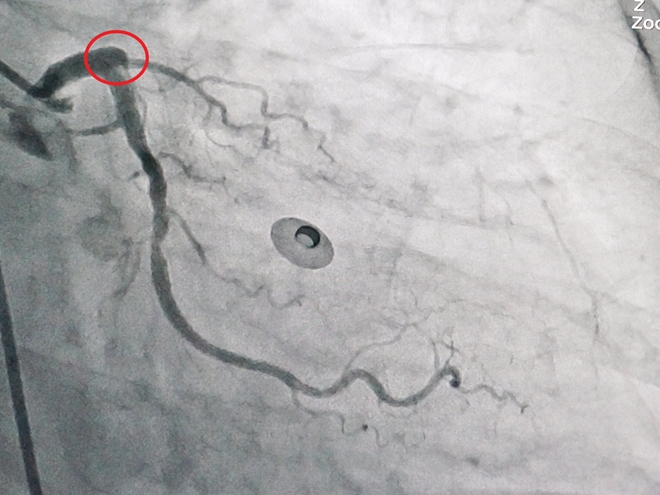

Bị tắc cả hai nhánh động mạch liên thất trước và nhánh động mạch vành trái lớn, tình trạng cụ bà N.T.T.( 60 tuổi, ngụ tại Huyện Thạnh Phú, Bến Tre) có nguy cơ tử vong rất cao nhưng rất may đã được các bác sĩ Bệnh viện Đa Khoa Xuyên Á can thiệp mạch máu kịp thời.